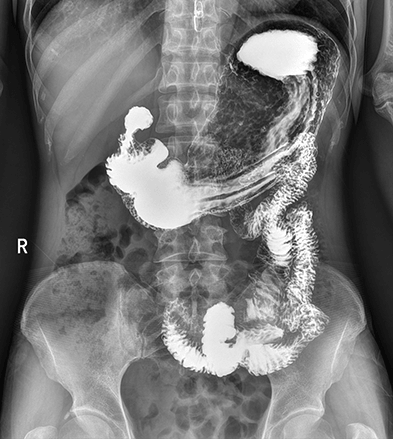

平板探测器

高清点片

DFP

同步曝光